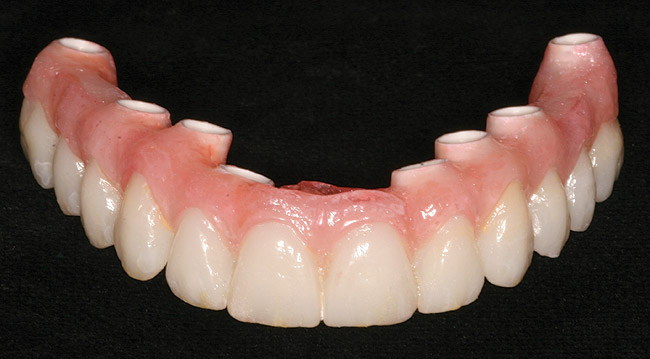

Figure 16  Laboratory-processed provisional restoration fabricated prior to surgery.

Figure 16

Figure 17  Provisional restoration placed at time of surgery.

Figure 17

Guided implant surgery involves reverse treatment planning. The ideal contour and arch position of the restoration is planned first, followed by virtual planning of the implant into that position according to the bony anatomy and clinical scenario. SLA surgical guides are then fabricated from the treatment plan. A dental laboratory next uses the SLA guide, with mounted casts, to fabricate provisional restorations prior to implant placement. At the time of surgery, the surgical guide is used to place the implants flaplessly, removing only a tissue core in the implant site(s). Abutments are immediately placed, and provisional restorations can be inserted.15-20 (Figure 12 through Figure 17).

Although technologies are available to place immediate definitive restorations, most clinicians are placing provisional restorations, for many reasons. Whether performed flaplessly or not, after surgery the final gingival contours and anatomy cannot be predicted. The clinician and dental technician can gain invaluable information as to the gingival contours and esthetics by observing tissue responses from the provisional restoration. Whether implant placement is guided or nonguided, a small number of implant failures occur. Most surgery-related failures take place within the first 3 to 4 months after implant placement. Surgical and restorative implant failure management is best accomplished prior to insertion of the definitive restoration. According to Abrahamsson et al, changing from a healing abutment to a permanent abutment did not result in a change in the dimension and quality of the transmucosal attachment that developed. It did not differ from the mucosal barrier that formed on a permanent abutment placed after surgery.31 An acrylic resin occlusal surface or a composite restoration reduces the forces of impact and has a better shock-absorbing behaviour compared to ceramic materials32; this is an additional reason for placing immediate acrylic resin provisional restorations, rather than immediate definitive porcelain restorations.